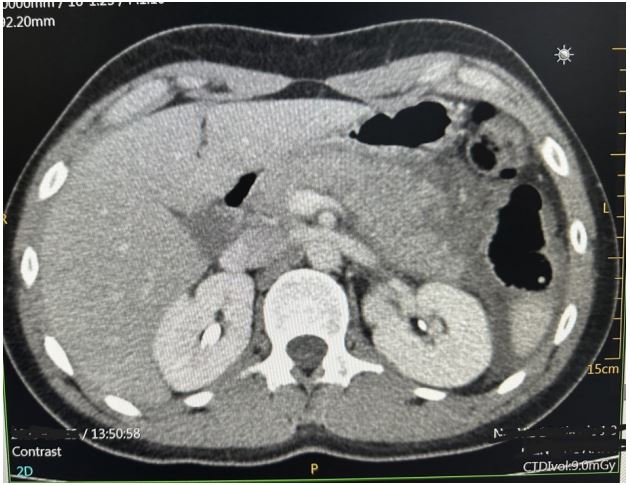

A Moroccan 17 year old male presented to the emergency department for four days of newly experienced epigastric pain associated to non-bloody and non-bilious emesis. The patient the child was diagnosed with epilepsy for which treatment with sodium valproate was initiated. The last dosage is changed nine months before from 750 mg to 1 g to maintain a dose of 20 mg/kg/d. There was no seizure the last year. On presentation he denied history of other new medications, supplements, alcohol or drug use, gallstones, fevers or chills. The epigastric pain was intense and resistant to anttispasmodic and oméprazole. Physical examination on arrival was notable for uncomfortable appearing, he complains of intense localized pain in the epigastrium radiating towards the back with an attitude of leaning forward. He was apyretic. On palpation we noted a focal epigastric tenderness with non-peritonitic abdomen. Respiratory and hemodynamic functions were stable. blood pressure 125/67, pulse 87, respiratory rate of 20, spo2 of 100%. The rest of the physical examination findings were unremarkable without any rashes, joint swelling, or adenopathy. Serum laboratory investigations in the emergency department revealed the following pertinent and significant findings: lipase level of 462 U/l, white blood cell count of 11.000 per mm3 , Activated protein C 27 mg/l, hemoglobin 10.6 g/dl, AST 28U/L, ALT 25U/L, Total bilirubin 8.2 mg/L, sodium 141 mmol/l, potassium 4.2 mmol/l, BUN 0.35 g/l, creatinine 10,2 mg/l, calcium 90 mg/l, and. All other initial laboratory invetigations within normal limits or insignificant. Patient was resuscitated with two liters of isotonic saline serum, received a total of 40 mg of intravenous omeprazole, 500 mg of intravenous paracetamol, and 4 mg of intravenous morphine. Initial abdominal ultrasound showed a normal gallbluddder, without any stones, gallbludder wall thickening, or common bile duct dilatation. the pancreas is globular with infiltration of gastric fat and presence of moderate peritoneal effusion (Figure 1). Subsequently, patient underwent a computed tomography of abdomen and pelvis with intravenous contrast (Figure 2). The pancreas was enlarged, had a homogeneous density, with a discreet homogeneous enhancement without an area of pancreatic parenchymal necrosis. presence of a peritoneal effusion of medium abundance surrounding the pancreas, perigastric, perihepatic, perisplenic level and in pelvic slope. The gallbladder, bile ducts, liver, spleen and kidneys were without abnormalities. The appearance was an acute edematous pancreatitis grade E of Balthazar. Patient was admitted to intensive care unit, he continued to receive intravenous boluses and maintenance fluids per standards of care for acute pancreatitis, along with adjunct therapies including antispasmodic, omeprazole and morphine to control pain. Food is reintroduced gradually from the 3rd day after the nausea and vomiting have disappeared and the pain has been controlled. we started with water, herbal teas, vegetable broths in small volumes. All this while monitoring digestive tolerance and the absence of pain. During the first days of hospitalization, patient underwent an extensive panel of investigations including bili-MRI showed the absence of stones in the Wirsung duct and bile ducts which are not dilated, no malformation or pancreatic mass is revealed (Figure 3). The other investigations were hematological toxicology screen, viral screening (including A, B and C hepatitis panel, respiratory viral panel, measles mumps rubella panel Epstein barr, cytomegalovirus panel), TPHA VDRL serology, tuberculosis quantiferon, lipid panel (cholesterol 1.46 g/L, triglycerids 0.9 g/L), blood smear, thyroid panel, antinuclear and anticardiolipin antibodies, hemoglobin electrophoresis; all returning either within normal or unremarkable limits. The absence of another cause responsible for pancreatitis led us to consider the drug etiology, particularly sodium valproate. Neurology consult was placed. Treatment with valproate of sodium was stopped and replaced by levetiracetam 250 mg twice a day. The opatient made a full recovery and was discharged after a total of eight days with prescription of levetiracetam. Any epileptic crisis was observed. The patient continue to have regular outpatient neurology follow up.

Figure 1: Abdominal ultrasound showed enlarged pancreas with infiltration of gastric fat and peritoneal effusion.